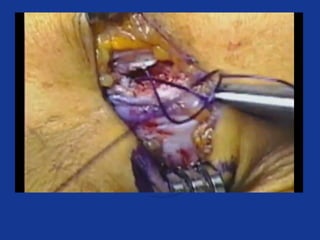

Open release

• Incision ant to lateral epicondyle

• ECRL posterior fascial edge lifted

• Degenerate tissue within ECRB excised

• Defect firmly repaired

– +/- suture anchors

• ?Decompression of PIN

• Excellent / good 75 – 91%

• Poor / failed 2 – 11%

• 80 – 95% return to normal activity in 4/12